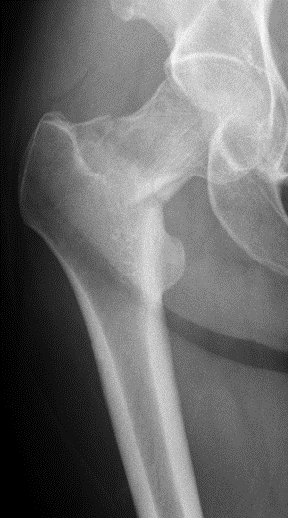

11 days ltr, pt returns to ER w/severe pain in (R) hip. What is the Dx? Pt has a displaced femoral neck Fx. She likely had a femoral neck stress Fx, which would have been Dx'd w/MRI. Once the Fx has completed, the course of Tx & Px change dramatically. What would you do now?

Pt has surgery at an outside hospital, where a surgeon performs a closed reduction and percutaneous screw placement, and is made non-weightbearing x 6 wks. Is this what you would do? How is the reduction? Which implant would you use? #OrthoTwitter #MedTwitter

8 wk follow-up xrays. Pt has persistent pain in the hip. What do you see? Is the fracture healing?

Pt has an impending femoral neck nonunion. She has varus collapse and shortening of the Fx. At this point, the Fx is unlikely to heal w/out intervention. Options include a total hip arthroplasty (THA) or a salvage procedure, namely a valgus intertrochanteric osteotomy.